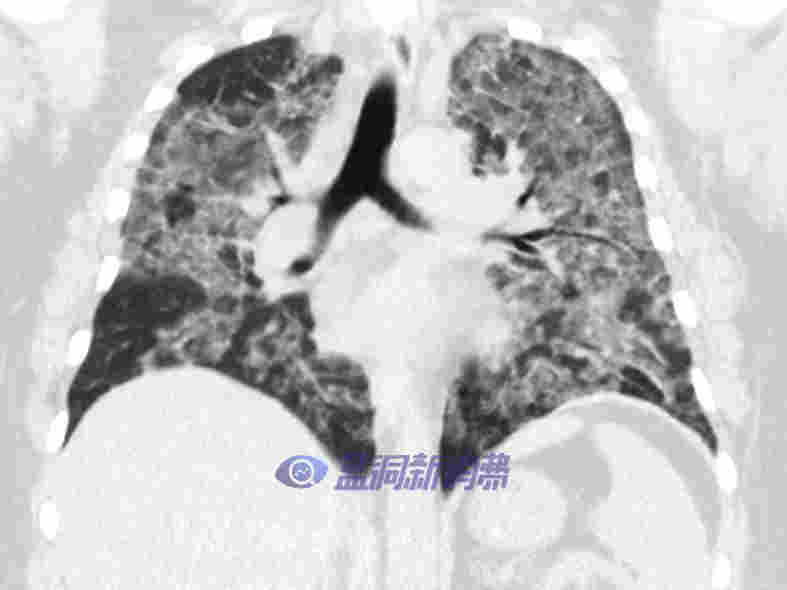

而在 2019 年更早些時候,美國多州也爆發與電子煙相關疾病,并在 2019 年 9 月達到巔峰。截至 2020 年 2 月 18 日,美國疾控中心共報告 2807 例與電子煙或霧化產品相關的肺損傷(evalI)病例,其中 68 例死亡。據報道,evalI 患者通常會出現嚴重的呼吸短促、胸痛、嘔吐、發燒和疲勞等癥狀,有些患者需要在重癥監護室配合呼吸機治療。CDC 分析認為,該疾病的爆發與患者使用含有四氫大麻酚 ( THC ) 的電子煙或電子煙產品有關,尤其是在該類產品中使用的維生素 E 醋酸酯。